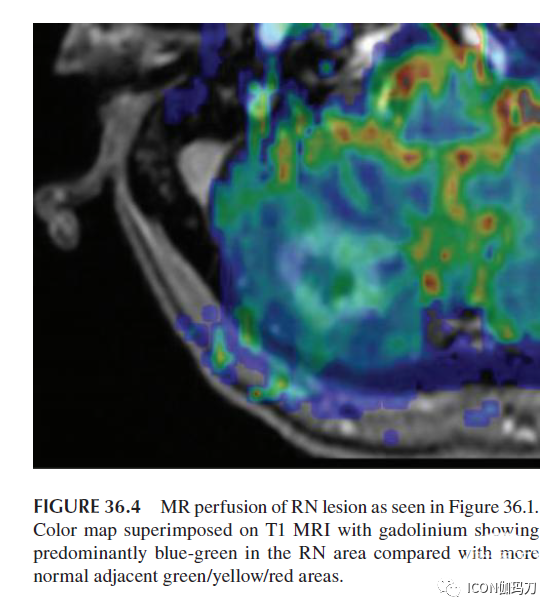

36.4.5 MR灌注

MR灌注使用动态敏感性加权对比增强成像来确定相对脑血容量(rCBV)。作为微血管密度的一种测量方法,rCBV在放射性坏死中通常会减少,因为小血管损伤是其发展的基础。相反,肿瘤再生长促进血管生成,促进细胞营养和生存,因此在MRI上增强rCBV,增加灌注。MR灌注是目前可用的影像学选择中首选的技术(图36.4)。其原因之一是它提高了空间分辨率,并在后期处理中对其结果进行颜色编码。区分肿瘤与放射性坏死的rCBV截断值也存在可变性,这种可变性可能不仅与所研究的病理不同有关,也可能与MR灌注技术本身的不同有关。这些技术包括动态磁化率对比(DSC)T2加权MRI灌注、动态对比增强(DCE) T1加权MRI灌注和动脉脊柱标记。深入理解MR灌注成像的复杂性超出了本章的范围。Mitsuya等报道采用DSC灌注获得的rCBV >2.1鉴别发性脑转移瘤的敏感性为100%,特异性为95%。然而,Barajas等报道,使用DSC灌注,rCBV截断值为1.75,并不是区分复发性多形性胶质母细胞瘤(GBM)与放射性坏死(敏感性79%,特异性72%)的可靠方法。Metaweh等对高级别脑胶质瘤的研究报道了相似的敏感性和特异性(78%和80%)。Zakhari等报道,使用DCE灌注,CBV仍然是肿瘤的最佳预测指标,肿瘤中位CBV为8.39,放射性坏死中位CBV为5.86。Chuang等人对13项研究的荟萃分析证实,对比增强病变中平均rCBV的肿瘤复发率明显高于放疗损伤。他们也证实在相同的研究中,肿瘤中Cho/Cr的平均比值再次较高,他们提出将MR波谱与灌注相结合以提高诊断的准确性。

图36.4 如图36.1所示RN(放射性坏死)病变的MR灌注。彩色图叠加T1 MRI加钆计显示RN区域以蓝绿色为主,而正常相邻的绿色/黄色/红色区域较少。